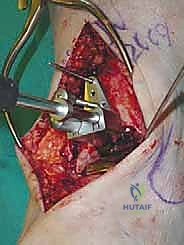

يقوم الدكتور هطيف بعمل شق طولي دقيق في الجزء الأمامي من الكاحل، طوله حوالي 10-15 سم. يتم تشريح الأنسجة بعناية فائقة للوصول إلى المفصل.

* الحماية العصبية الوعائية: هذه هي الخطوة الأكثر حرجاً. يتم تحديد الحزمة الوعائية العصبية (الشريان الظنبوبي الأمامي والعصب الشظوي العميق) وسحبها برفق شديد لحمايتها من أي ضرر جراحي.

3. إزالة النتوءات العظمية وتحضير المفصل (Debridement)

بمجرد كشف المفصل، يقوم الجراح بإزالة الغشاء الزلالي الملتهب والزوائد العظمية (Osteophytes) التي تعيق الحركة. هذه الخطوة ضرورية لاستعادة المعالم التشريحية الطبيعية قبل إجراء القطع العظمي.